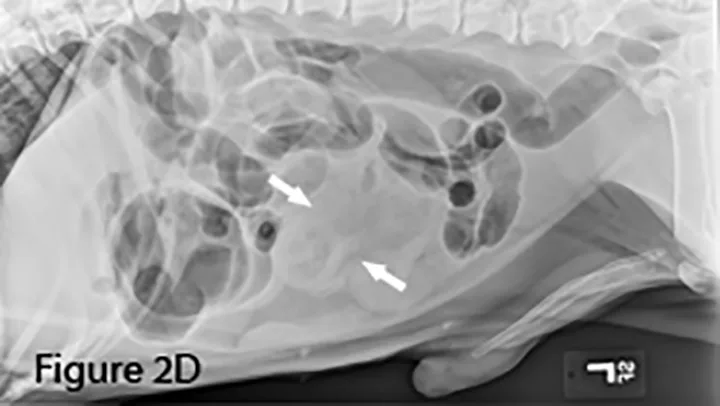

Marked diffuse small intestinal dilation (arrows). (C = colon)

Invagination of 1 portion of the GI tract (intussusceptum) into the lumen of another (intussuscipiens); this is often referred to as the target sign when seen in the transverse plane because of the multiple layers of adjacent intestinal walls.